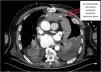

A 66-year-old patient on the second day after biological mitral valve replacement surgery due to severe periprosthetic insufficiency. While extubated, he developed tachycardia, hypoperfusion and hyperlactacidemia, with the need for vasopressor medication and the deobstruction of drains due to large clots, followed by clinical improvement. This was followed by repeat worsening with the same clinical manifestations, requiring intubation and vasopressor medication. Transesophageal ultrasound showed an anterior hyperdense mass with a minimal right atrial imprint (Fig. 1) and left massive pleural effusion at apical-middle and basal level, with “hematocrit sign” (Fig. 2). The thoracic CT scan showed an anterior mediastinal hematoma with posterior communication with the left pleura, and contrast leakage at the internal mammary artery level (Fig. 3), requiring urgent surgery and polytransfusion (see Supplementary material). In recent years, transesophageal pulmonary ultrasound has experienced marked development in critical patients, affording an excellent complementary tool for assessing the posterior and deep regions of the lung with increased imaging quality.